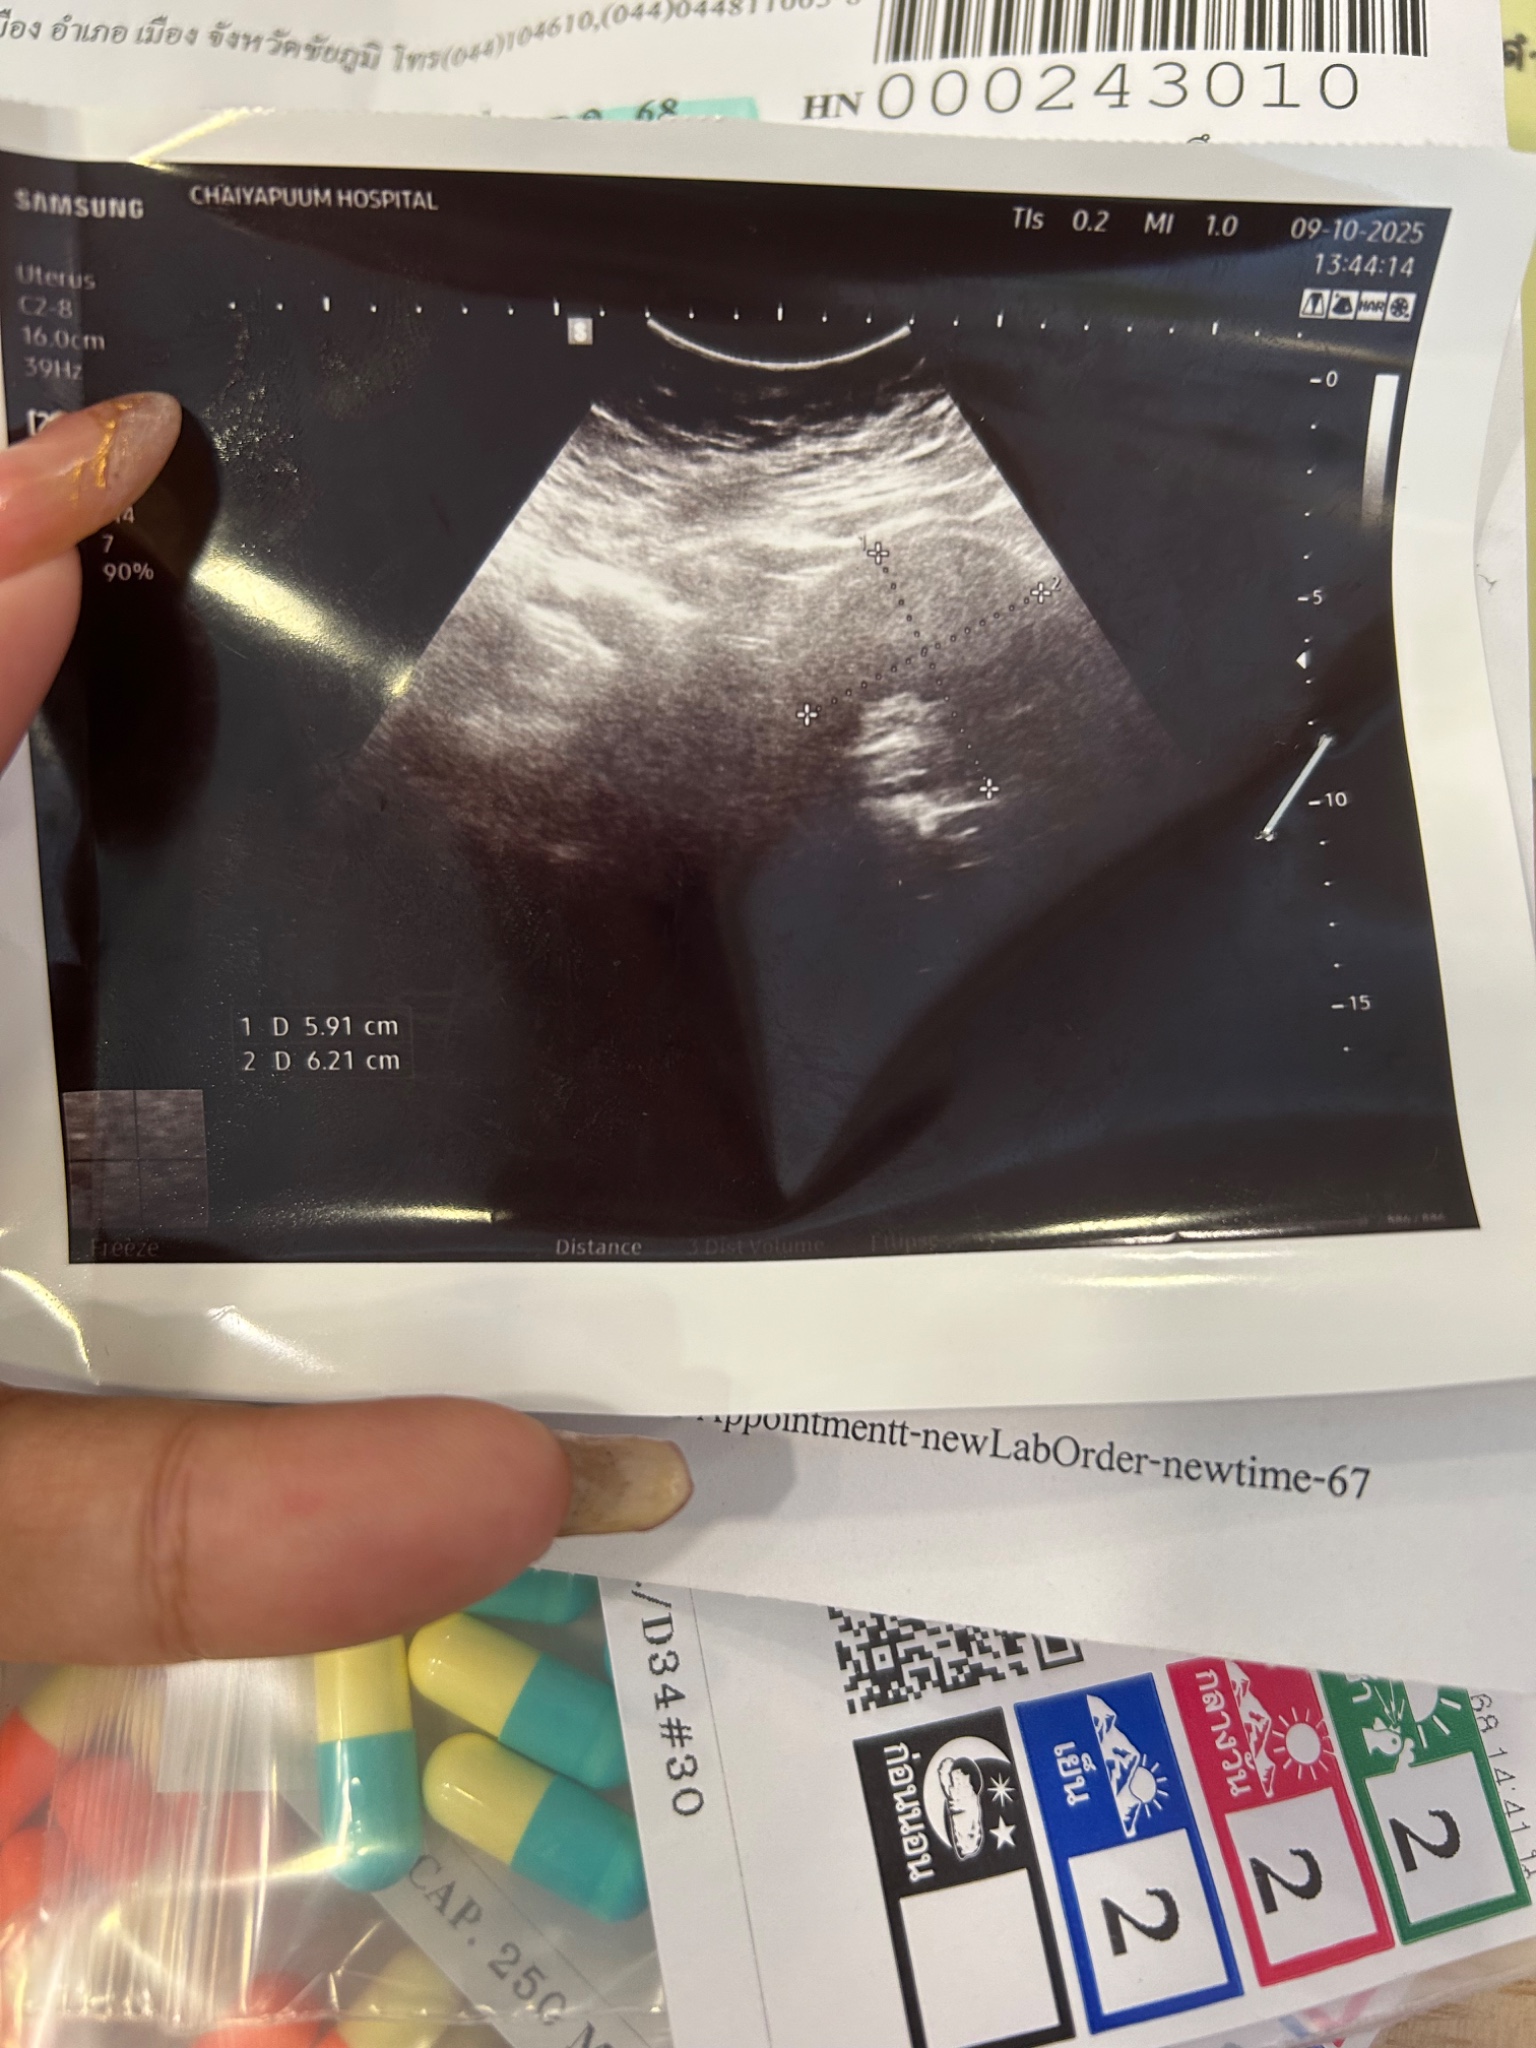

ขอถามเป็นความรู้หน่อยคะ พอดีว่าเป็นประจำเดือน2เดือนคะมาแบบทุกๆวัน แล่วเป็นลิ่มเลือดออกมาเป็นก้อนมาตลอด2เดือแล้วมีอาการปวดท้องหน่วงท้องตลอดมาวันนี้เหมือนจะวูบเหนื่อยง่ายหลังๆมานี้วันนี้เลยเข้าตรวจที่โรงบาลคะ อัลตร้าซาวแล้ว หมอคิดว่าอาจจะเป็น ระหว่างซีสกับเยื่อบุโพรงมดลูกเจริญผิดที่คะ ช่วยดูฟิล์มแล้วบอกตามที่ดูหน่อยได้มั้ยคะว่ามีสิทธิ์จะเป็นอะไรมากกว่ากันคะ แล้ววันนี้หมอตรวจภายในด้วยคะทั้งที่เป็นประจำเดือนอยู่แล้วปวดท้องมากๆด้วยคะหลังออกจากห้องตรวจต้องกลีบไปที่โรงบาลอีกมั้ยคะหรือว่าต้องรอดูไปก่อน ก้อนในมดลูกมีขนาดประมาณ5-6ซมฺได้คะ